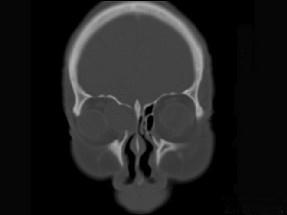

问题 女性38岁,右侧眼球运动障碍伴眼球突出4个多月,CT扫描如图,请选择正确的描述和答案 ( )

选项 A、考虑为右侧筛窦黏液囊肿 B、考虑为筛窦癌 C、囊性肿块向右侧眼眶内突入,压迫内直肌 D、右侧眶内壁呈受压变薄、断裂 E、右侧筛窦内可见囊性肿块影,边缘光整

答案 ACDE